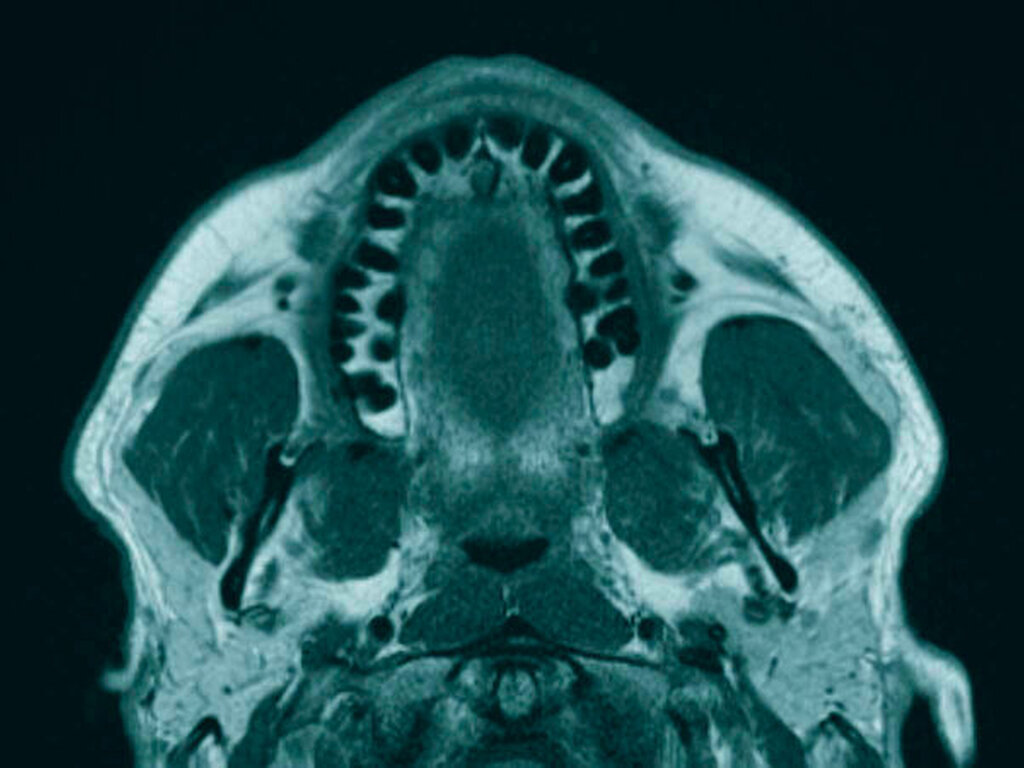

Anschließend wurde zur Ausbreitungsdiagnostik eine Magnetresonanztomografie (MRT) der Kopf-Hals-Weichteile mit Kontrastmittel durchgeführt (Abbildung 2). Hierbei kam eine malignomsuspekte Raumforderung im Oberkiefer im Bereich der regiones 11 bis 21 zur Darstellung, metastasensuspekte Auffälligkeiten der Halslymphknoten konnten nicht ausgemacht werden. Nach Besprechung des Falles in der interdisziplinären Tumorkonferenz wurde der Befund lokal mit Sicherheitsabstand in toto exzidiert und die mit der Raumforderung kommunizierenden Zähne 12, 11 und 21 extrahiert (Abbildung 3).

Die Ausbreitungsdiagnostik des OMM ist abhängig vom jeweiligen Stadium und analog zum kutanen malignen Melanom, dabei nimmt das Melanoma in situ wiederum eine gesonderte Rolle ein. Neben einer sonografischen Untersuchung der Halsweichteile kann eine Magnetresonanztomografie (MRT) der Kopf-Hals-Region zur Beurteilung der lokoregionären Ausdehnung und der Halslymphknoten, wo in der Regel zuerst Metastasen auftreten, durchgeführt werden [Medina et al., 2003]. Generell wird jedoch in frühen Stadien keine direkte Empfehlung für eine Schnittbildgebung ausgesprochen. Zur Ausbreitungsdiagnostik beim Melanoma in situ reicht laut Leitlinie die klinische Untersuchung aus. Wohingegen im fortgeschrittenen Stadium eine MRT Kopf, eine Ganzkörperschnittbildgebung mittels PET-CT, CT oder MRT, eine Skelettszintigrafie und die Bestimmung der Tumormarker S100B und LDH dazukommen [Eigentler et al., 2020]. Zu beachten ist dabei, dass aufgrund der Seltenheit des OMM nur geringe Evidenzlevel der Empfehlungen vorliegen, die auf einem Expertenkonsens und nicht auf randomisiert kontrollierten Studien beruhen.